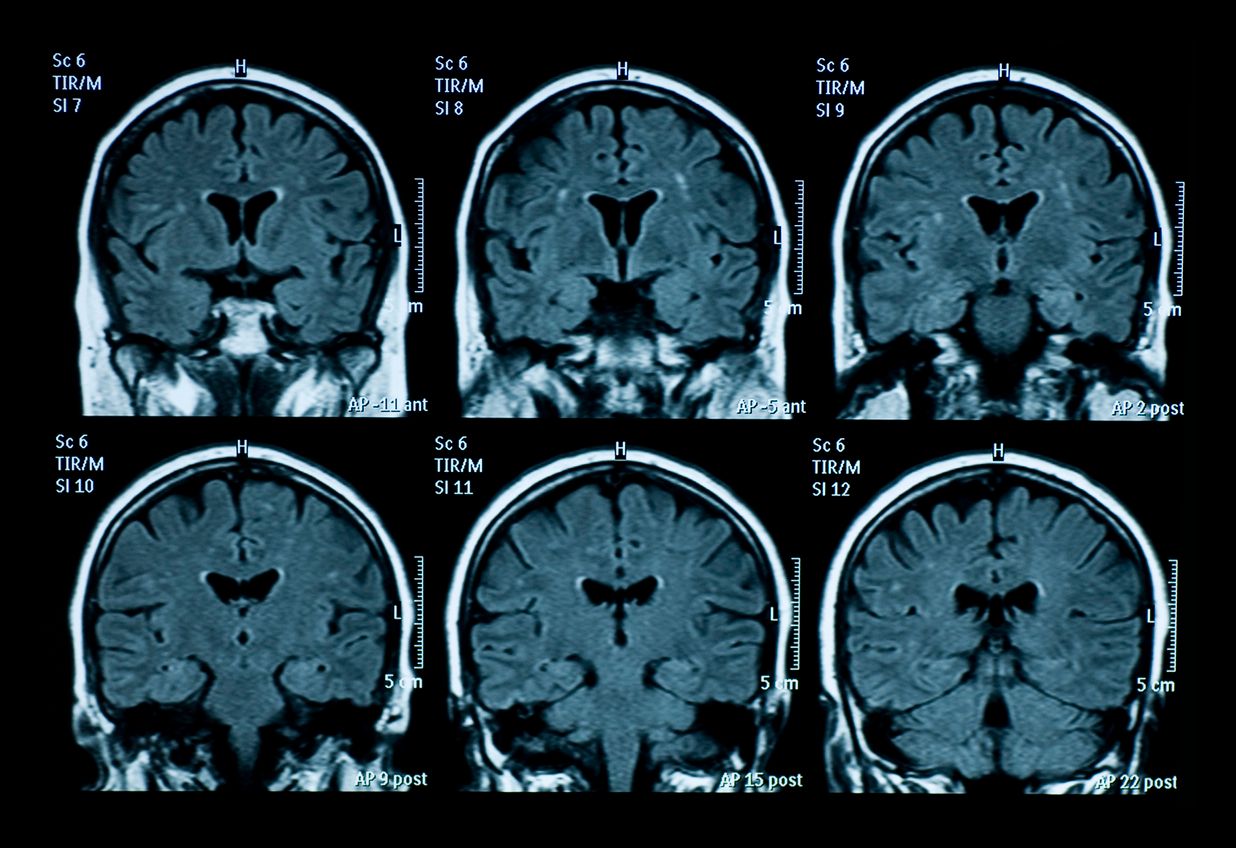

Prionenkrankheiten sind "eine Familie seltener progressiver neurodegenerativer Erkrankungen, die sowohl Menschen als auch Tiere betreffen." (Symbolbild)